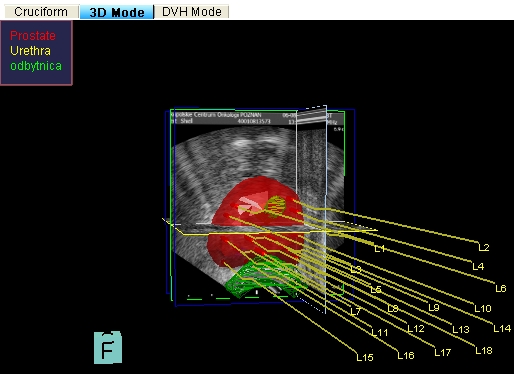

Obraz igieł 3D - widoczny zarys USG gruczołu krokowego (kolor czerwony)